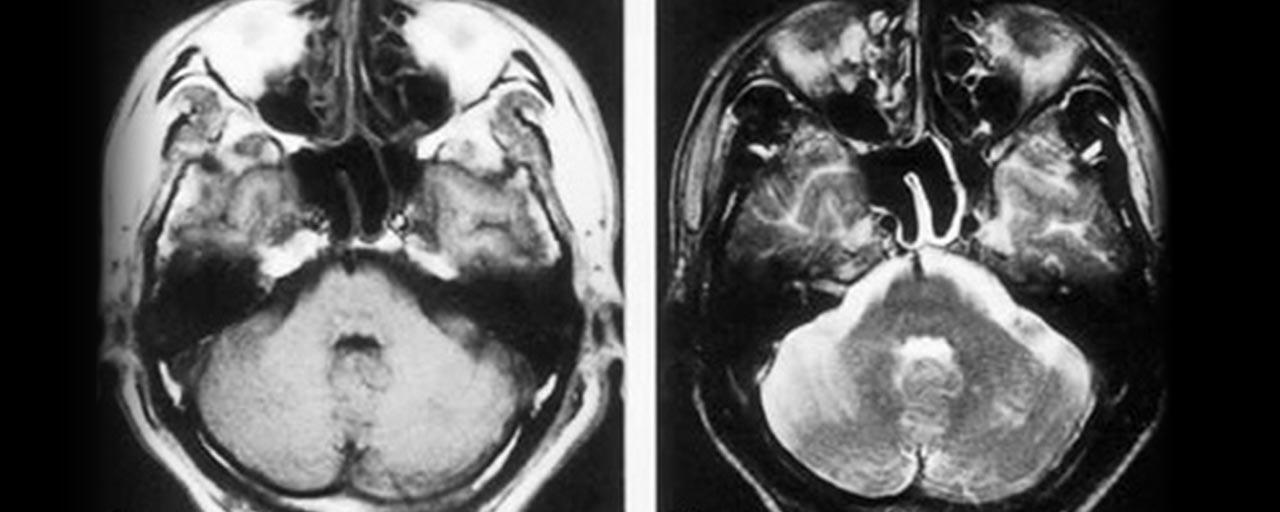

脳動脈解離

脳動脈がさけることにより、急性に血管の閉塞をきたすことがある。

特に椎骨脳底動脈系で生じやすく、若年者の脳梗塞の原因となる為、

若年者の頭痛を伴うワレンベルグ症候群を見た場合はまず脳動脈解離を疑う事が重要である。

頸部の過伸展やスポーツなどの外傷で生じる事がある。

画像所見はMRIでT1画像で動脈壁の三日月状高信号(壁在血栓)やMRAで

pearl and strings signやflap形成が見られる。